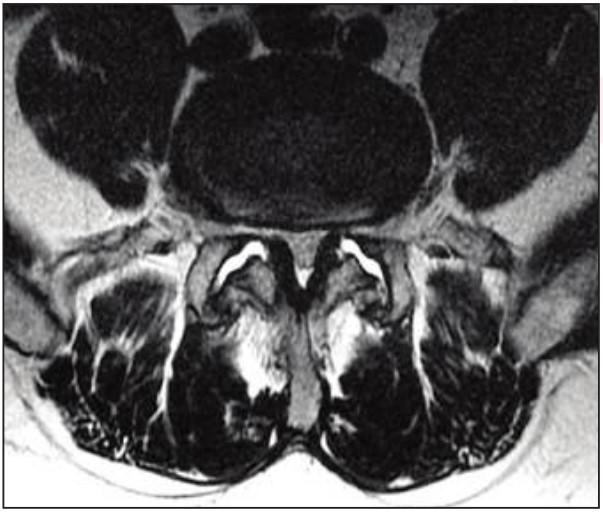

A convolutional neural network can accurately measure skeletal muscles, helping predict patient survival.